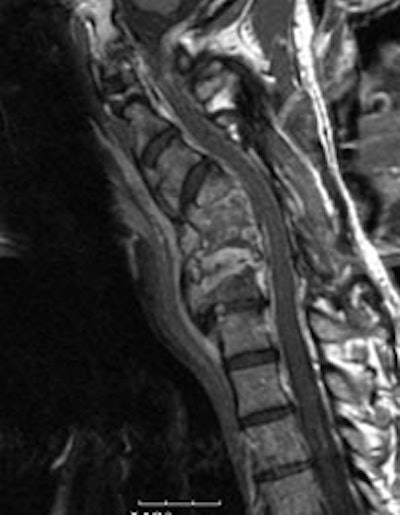

Cervical spine discitis and osteomyelitis: The case below is an example of the decreased sensitivity of In-111 WBC imaging for spinal infection. The MR images show abnormal disc enhancement at the C6-7 level consistent with discitis and enhancement of the C7 vertebral body consistent with osteomyelitis (white arrows). Post-gadolinium images are on the left. An In-111 WBC and Tc99m-Sulfur colloid exam in the same patient demonstrates a photopenic defect (black arrows) corresponding to the area of infection confirmed on the MR exam (white blood cell images are on the left). A defect on Tc-sulfur colloid imaging is seen with osseous infection due to marrow infiltration with inflammatory cells and edema which obstructs small arterioles. Click images to enlarge. |

|